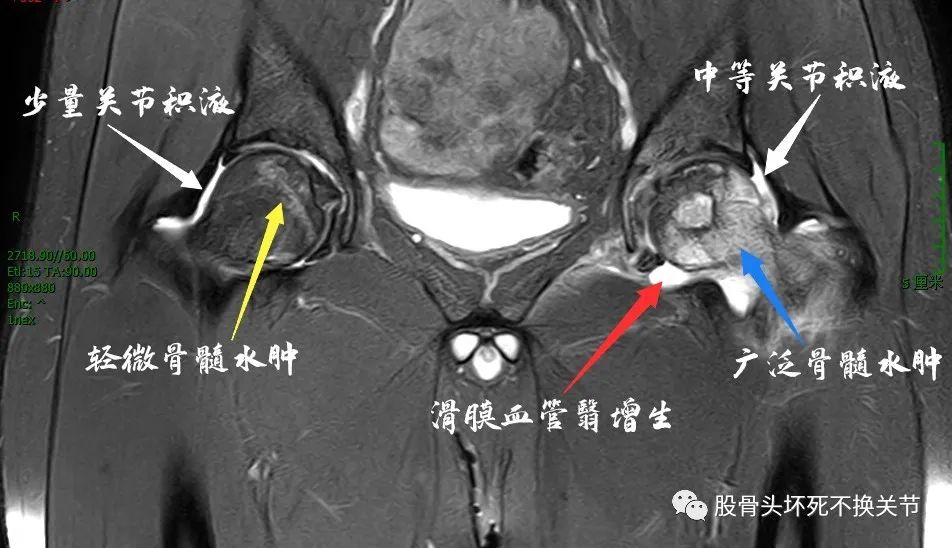

因患者自带MRI检查序列不完善,予以重新进行磁共振检查:

如上,右侧股骨头骨髓水肿很轻微,关节少量积液,暂时没有症状;左侧,股骨头内“白花花”的一片,提示为严重骨髓水肿,此外,还可以看到关节内大量关节积液、滑膜增生。

上图,黄色虚线内即为股骨头周围增生的滑膜血管翳,其对股骨头的不利作用显而易见。另外,软骨面、盂唇尚未发生明显病变。